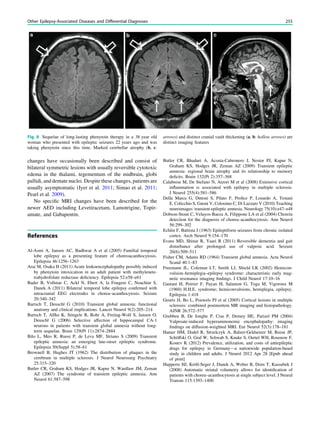

Fig. 2 Epileptogenic lesion and symptomatogenic zone. A 40-year-

old woman suffered from complex focal seizures with a fearful face

and body rocking. The symptoms thus pointed to the mesial frontal

lobe as the origin. MRI shows right-sided hippocampal sclerosis

(a, arrow). Simultaneous video and EEG recordings from interhemi-

spheric (c) and convexity strip and intrahippocampal depth (b) elec-

trodes show seizures starting in the right hippocampus (d, arrow).

Clinical symptoms start around 1 s afterwards (d, asterisk)